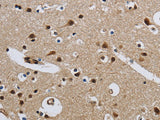

Applications IHC

IHC 1:50-1:200